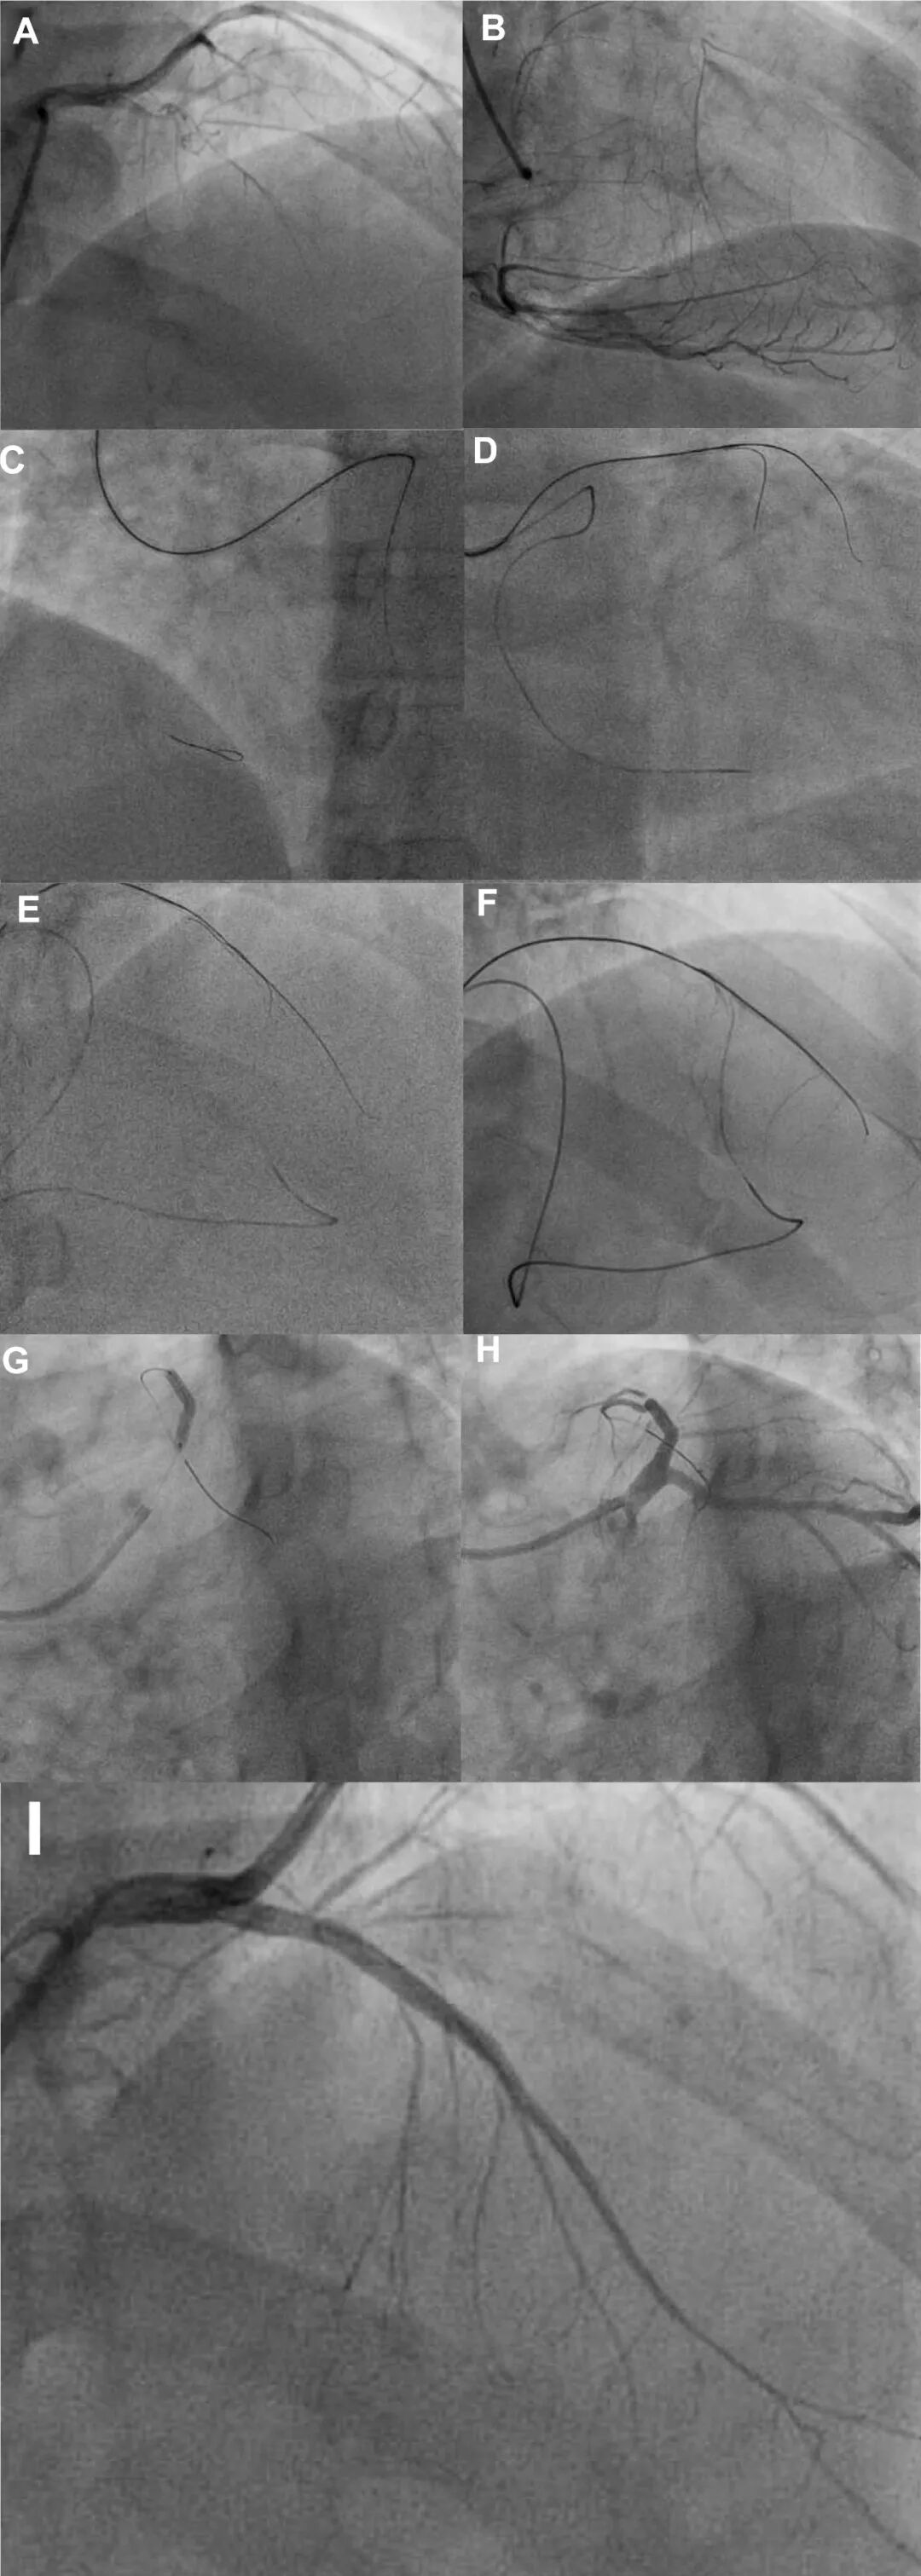

图7 ZHANG Bin技术在LAD-CTO中的应用

(A)LAD开口近端CTO病变。(B)发育良好的室间隔侧支血管供应LAD远端。(C)工作导丝成功从左侧指引导管进入右冠脉开口,随后深入至后降支。(D)150厘米的Corsair Pro微导管成功从左侧指引导管飞跃主动脉,进入右冠脉开口,并向远端推进至后降支。(E)逆向Sion Black导丝成功穿过室间隔侧支血管(侧支分级CC2)到达LAD远端。随后,在逆向导丝的引导下,ConquestPro 12导丝成功穿透CTO部位并推进至LAD远端。(F)冒烟确认正向导丝位于真腔内。(G)一枚药物支架成功植入LAD近端。(H和I)最终结果。